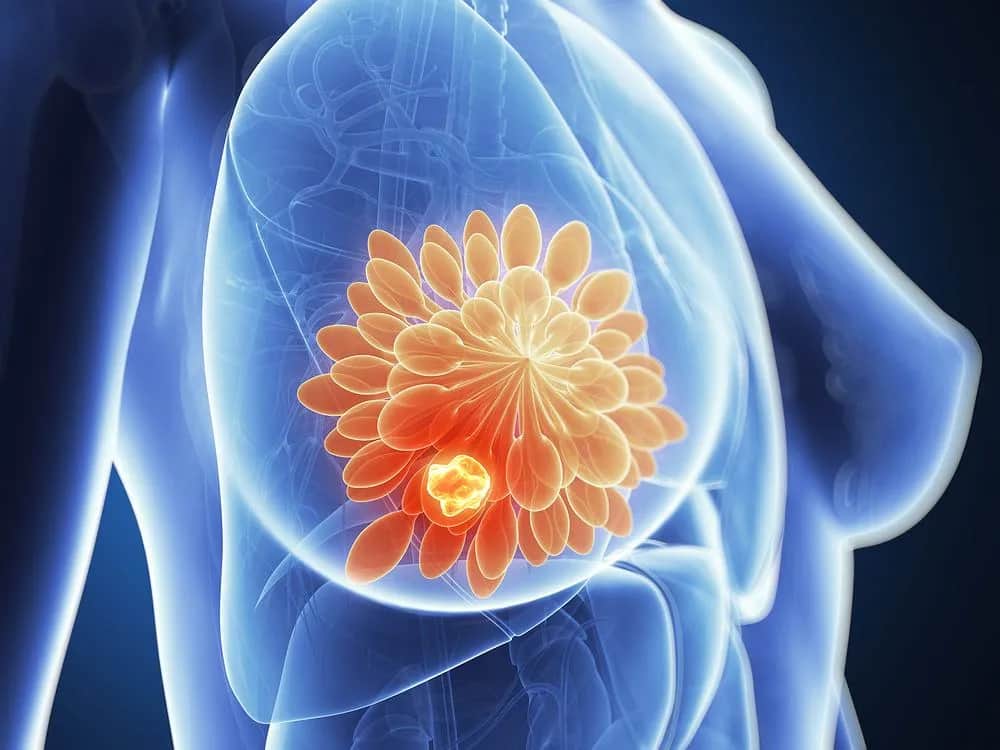

Poznaj skutki uboczne herceptyny, w tym działania niepożądane trastuzumabu i efekty leczenia. Dowiedz się, jak monitorować zdrowie przy terapii.